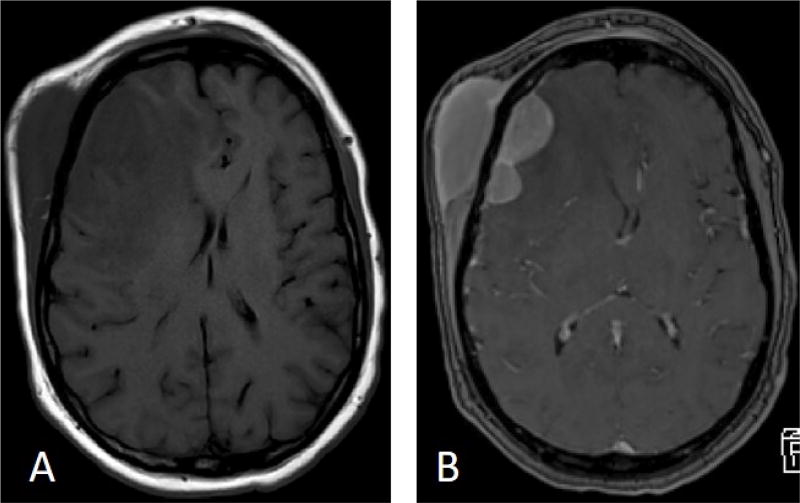

淋巴瘤表现为头皮肿块是一种罕见但严重的医学状况,需要积极治疗和神经外科干预。我们报告一个53岁的男性病例,他表现为右侧额部头皮肿块大,左侧额部头皮肿块小。在与患者讨论后,决定切除较大的肿块以确定诊断。肿块次全切除后,活检显示WHO 1级滤泡性淋巴瘤(FL),弥漫性IV期。患者随后接受了4格(Gy)的姑息性放疗,分2段对右侧额叶头皮进行放疗,并进行全身化疗免疫治疗(6个周期),随后进行了美罗华维持治疗。治疗开始一个月后进行腰椎穿刺取脑脊液,结果为恶性细胞扩散阴性。治疗开始约3个月后,PET/CT未显示活动性恶性肿瘤,MRI显示右侧额叶头皮肿物内部完全消退。我们用这个病例提供关于疾病病理生理,早期诊断和管理的详细讨论。

Lymphoma presenting as a scalp mass is a rare but serious medical condition mandating aggressive treatment and neurosurgical intervention. We report a case of 53-year-old male who presented with a large right sided frontal scalp mass and a smaller mass located on the left frontal scalp. After discussion with the patient, it was decided to resect the larger mass for definitive diagnosis. After subtotal resection of the mass, biopsy revealed WHO grade 1 follicular lymphoma (FL), diffuse pattern stage IV. The patient was subsequently treated with 4 grays (Gy) of palliative radiotherapy over 2 fractions to the right frontal scalp and systemic chemo-immunotherapy (6 cycles) followed by rituximab maintenance. Lumbar puncture to obtain cerebrospinal fluid was done a month after therapy began and the results were negative for spread of malignant cells. Approximately 3 months after initiation of therapy, PET/CT showed no evidence of active malignancy and MRI revealed a complete internal resolution of the enlarged right frontal scalp mass. We use this case to provide a detailed discussion regarding disease pathophysiology, early diagnosis, and management.